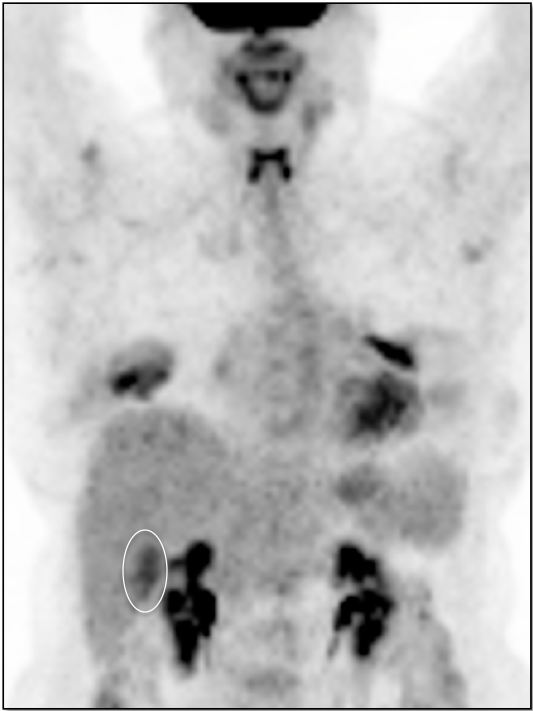

- Non-Attenuation Corrected Images

Value of NAC PET Images

- Resolving AC Artifacts

- Lung Nodule Identification